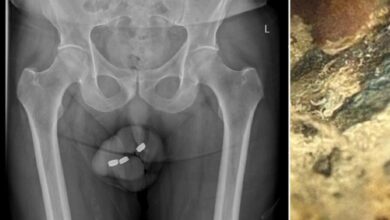

Απίστευτο: 73χρονος ικανοποιούνταν βάζοντας μπαταρίες στο…

Ένας 73χρονος άνδρας από την Αυστραλία χρειάστηκε να υποβληθεί σε χειρουργική επέμβαση στην ουρήθρα, προκειμένου να αφαιρεθούν από το εσωτερικό…